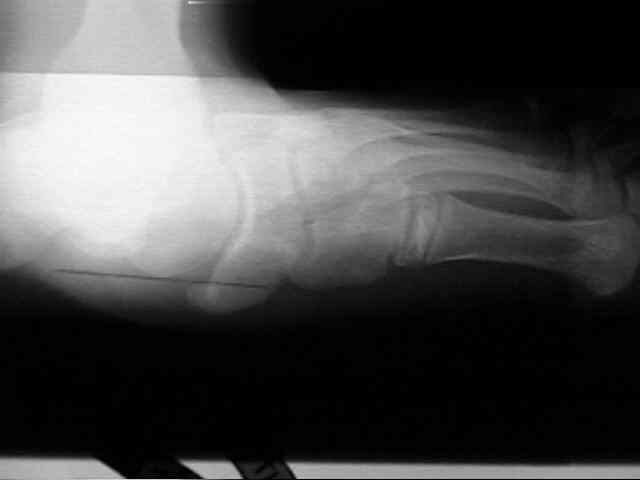

Radiographs

• radiographs may not be helpful if the accessory ossification is not ossified;

• the standard oblique of the foot (medial internal oblique view) will not show the accessory ossicle in profile;

• the lateral (external) oblique view is the radiograph of choice;

• although accessory navicular appears distinct from the navicular on x-rays, it is actually attached by fibrous tissue or cartilage;

Accessory Navicular 2 Accessory Navicular 3 Accessory Navicular 4